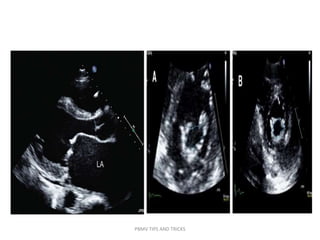

PBMV TIPS AND TRICKS